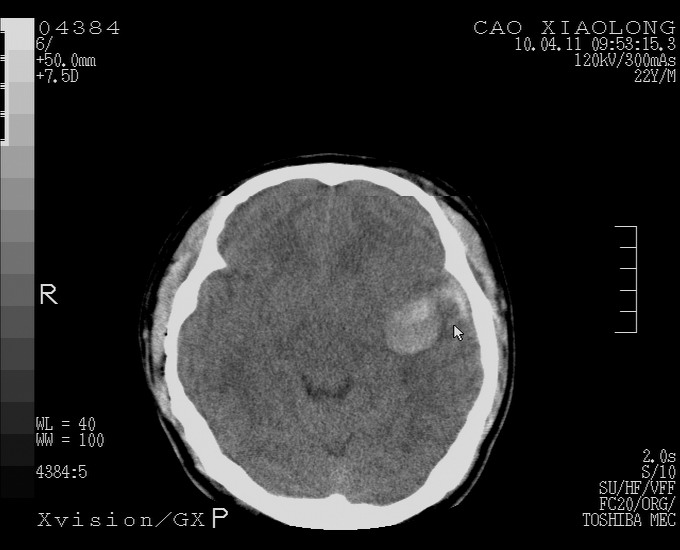

以下是引用随光逐影在2010-4-11 11:00:00的发言:[br]1)左侧额颞顶部硬膜下血肿。2)蛛网膜下腔出血。3)右侧颞顶部颅骨线形骨折。[br][br]20小时后复查:左侧额颞叶脑挫裂伤;左侧额颞顶部硬膜下血肿及蛛网膜下腔出血有吸收表现;右侧颞顶部颅骨线形骨折。[br]